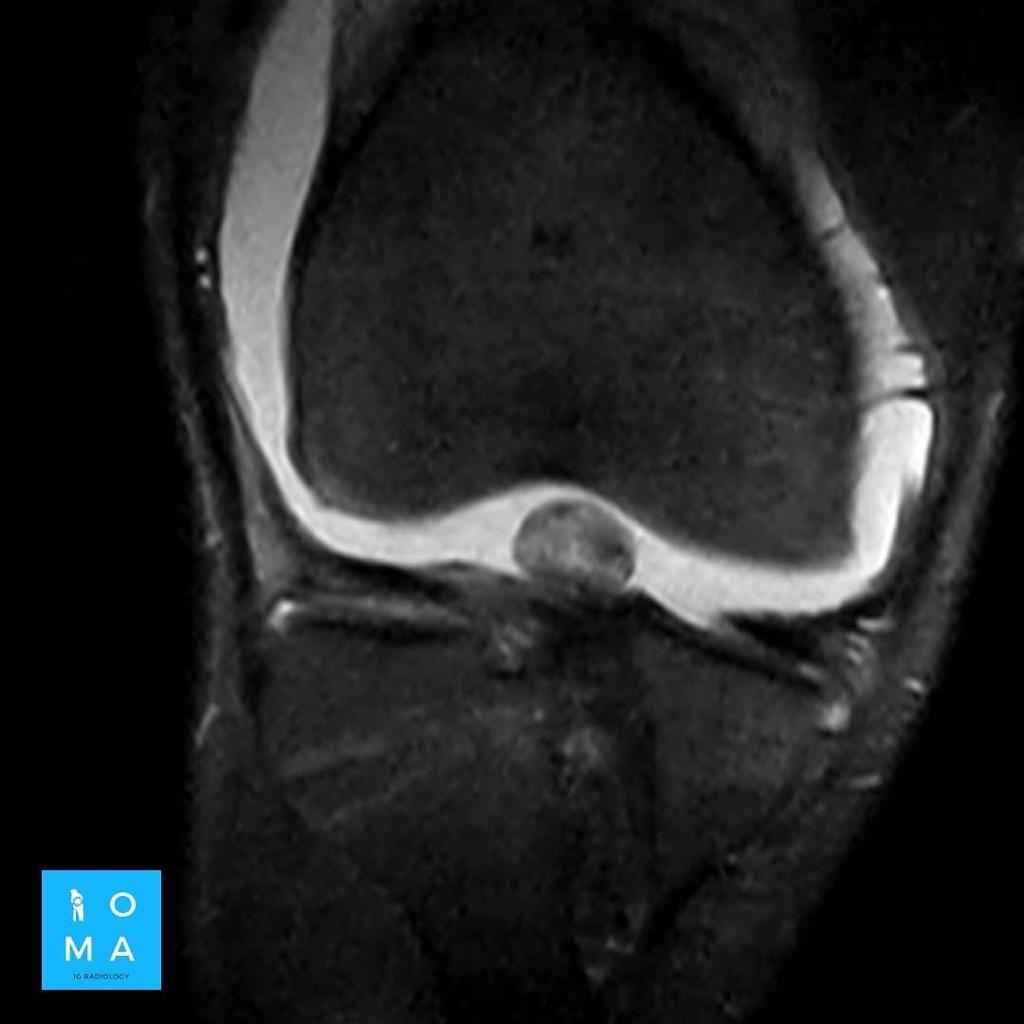

La evaluación hepatica entre Adenoma y HNF por resonancia magnética y su diferenciación con hepatocarcinoma puede ser difícil en ciertos casos aún, con el uso de contraste hepato especifico.

Se presenta caso de paciente de la 3a década, que en su embarazo se diagnostica con sospecha de adenoma y posterior al embarazo se realiza estudio de control contrastado para su mejor diferenciación.

En la evaluación con medio de contraste, se evalúa la relación arterial y de las venas, esto puede servir para buscar la arteria central relacionada con la hiperplasia nodular focal o bien, para evaluar la relación con las estructuras vasculares que son muy importantes para el planeamiento quirúrgico .

en este caso, aún cuando los hallazgos son atípicos tanto para hiperplasia nodular focal como para adenoma, nos inclinamos hacia el diagnóstico de adenoma debido a los antecedentes de la paciente, el tamaño de la lesión, el área de sangrado, el contenido de grasa.